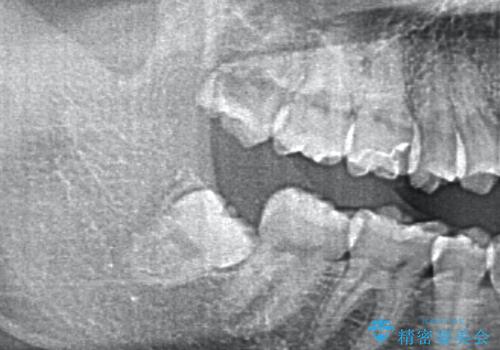

歯の高さを出すための親知らず抜歯と歯肉切除

担当医 岡田康成